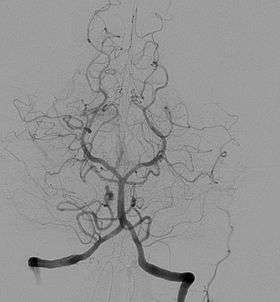

Angiogram showing a transverse projection of the vertebrobasilar and posterior cerebral circulation. | |

Another increasingly common angiographic procedure is neuro-vascular digital subtraction angiography in order to visualise the arterial and venous supply to the brain. Intervention work such as coil-embolisation of aneurysms and AVM gluing can also be performed.